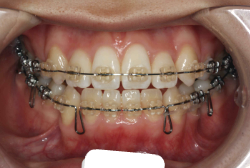

「ものがうまく噛めない」という主訴で来院したケースです。診断の結果、「骨格性反対咬合に伴う咬合不良+軽度叢生」と判明しました。原因としては特に下顎の左側が過成長したため、骨格性反対咬合になり、特に左側での噛み合わせが非常に悪くなっていると診断しました。初診時の写真を見ると、上下の正中線の大きなズレ、左側の噛み合わせの不良がはっきり分かります(黄色の矢印と緑の矢印は一致しているのが正しい状態です)。

そもそも、このような状態となっているのは骨の大きさに問題があるため生じていますので、場合によっては、「外科矯正」によって下顎の骨を外科的に縮めることで修正します。患者様が外科矯正をご希望されない場合は、従来ですと上下左右の小臼歯抜歯を行い矯正するのが普通です。

今回の患者様の場合は、「外科」も「小臼歯抜歯」も拒否されましたので、歯科矯正用アンカースクリュー(以下 アンカースクリュー)を用いて、下顎の歯列全体を後方に下げるという方法を取りました。

治療中の写真で、アンカースクリューより歯を後ろへ牽引しているのがお分かりいただけるかと思います。牽引を1年ほど続け、途中補助的に上下にゴムをかける(これを顎間ゴムと言います)手法なども追加し、全体で21ヶ月で治療を終えることが出来ました。

結局歯の本数を減らすことなく、すべてご自分の歯を残して、正しい配列と噛み合わせにすることができました。凸凹があまりひどくないため、簡単そうに見えると思いますが、このケースの初診の状態を見ると、熟練の矯正歯科医でも悩みのつきないケースです。まして、外科も出来ない、抜歯もイヤ、と言うことになると、従来の方法では治療不可能と考えられるのですが、アンカースクリューを使うことで最近は不可能が可能となってきました。